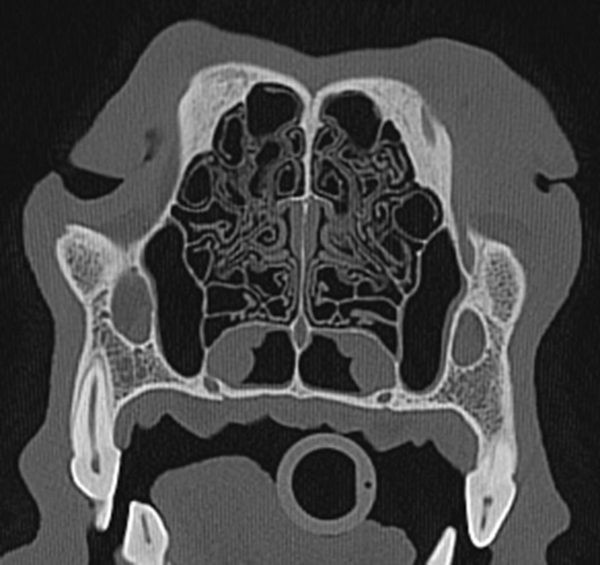

Computed tomography or CT of a dog nose.

Dog nose

CT imaging strength lies in its ability to image quickly for chest and abdominal studies so that images are not affected by the pet’s breathing. Exquisite bone detail is easily obtained for skull, sinuses, spine or limb studies.